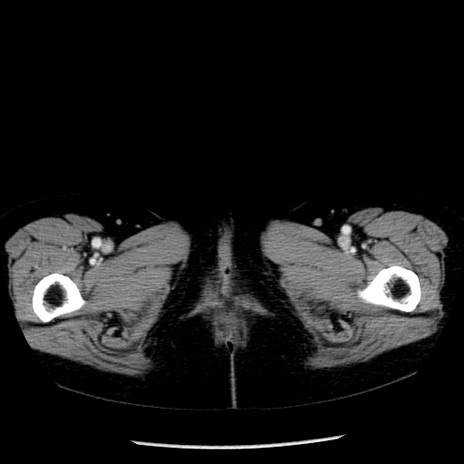

症例13(横断像)

【症例】70歳代女性

【主訴】腹痛、嘔吐

【現病歴】15時間程前(昨晩)より腹痛あり。今朝になっても症状の改善なく、嘔吐あり。腹痛も増悪あり、救急外来受診。

【既往歴】子宮癌全摘術後

【身体所見】意識清明、BP 121/72mmHg、P 74bpm、SpO2 100%(RA)、腹部:平坦・軟、腸雑音ほぼ聴取せず。下腹部・心窩部・臍左上に圧痛あり。反跳痛なし。

【データ】WBC 10600、CRP 0.15